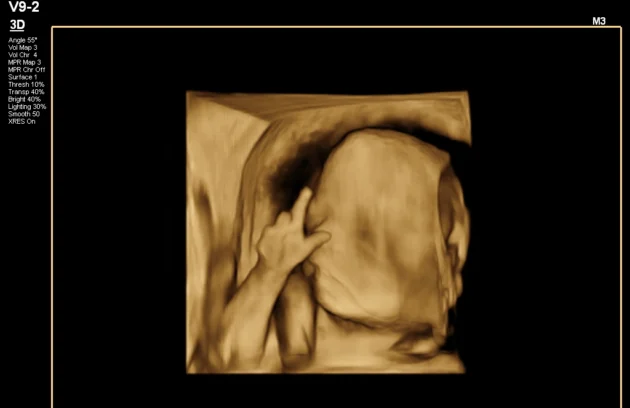

🔹 3D / 4D Ultrasound

3D/4D Ultrasound provides a clear and real-time view of your baby inside the womb. While 3D shows detailed images, 4D allows you to see live movements like smiling or yawning. It enhances bonding between parents and baby while also helping doctors assess physical development. Experience advanced 4D ultrasound in Kathmandu for a memorable and informative pregnancy journey.